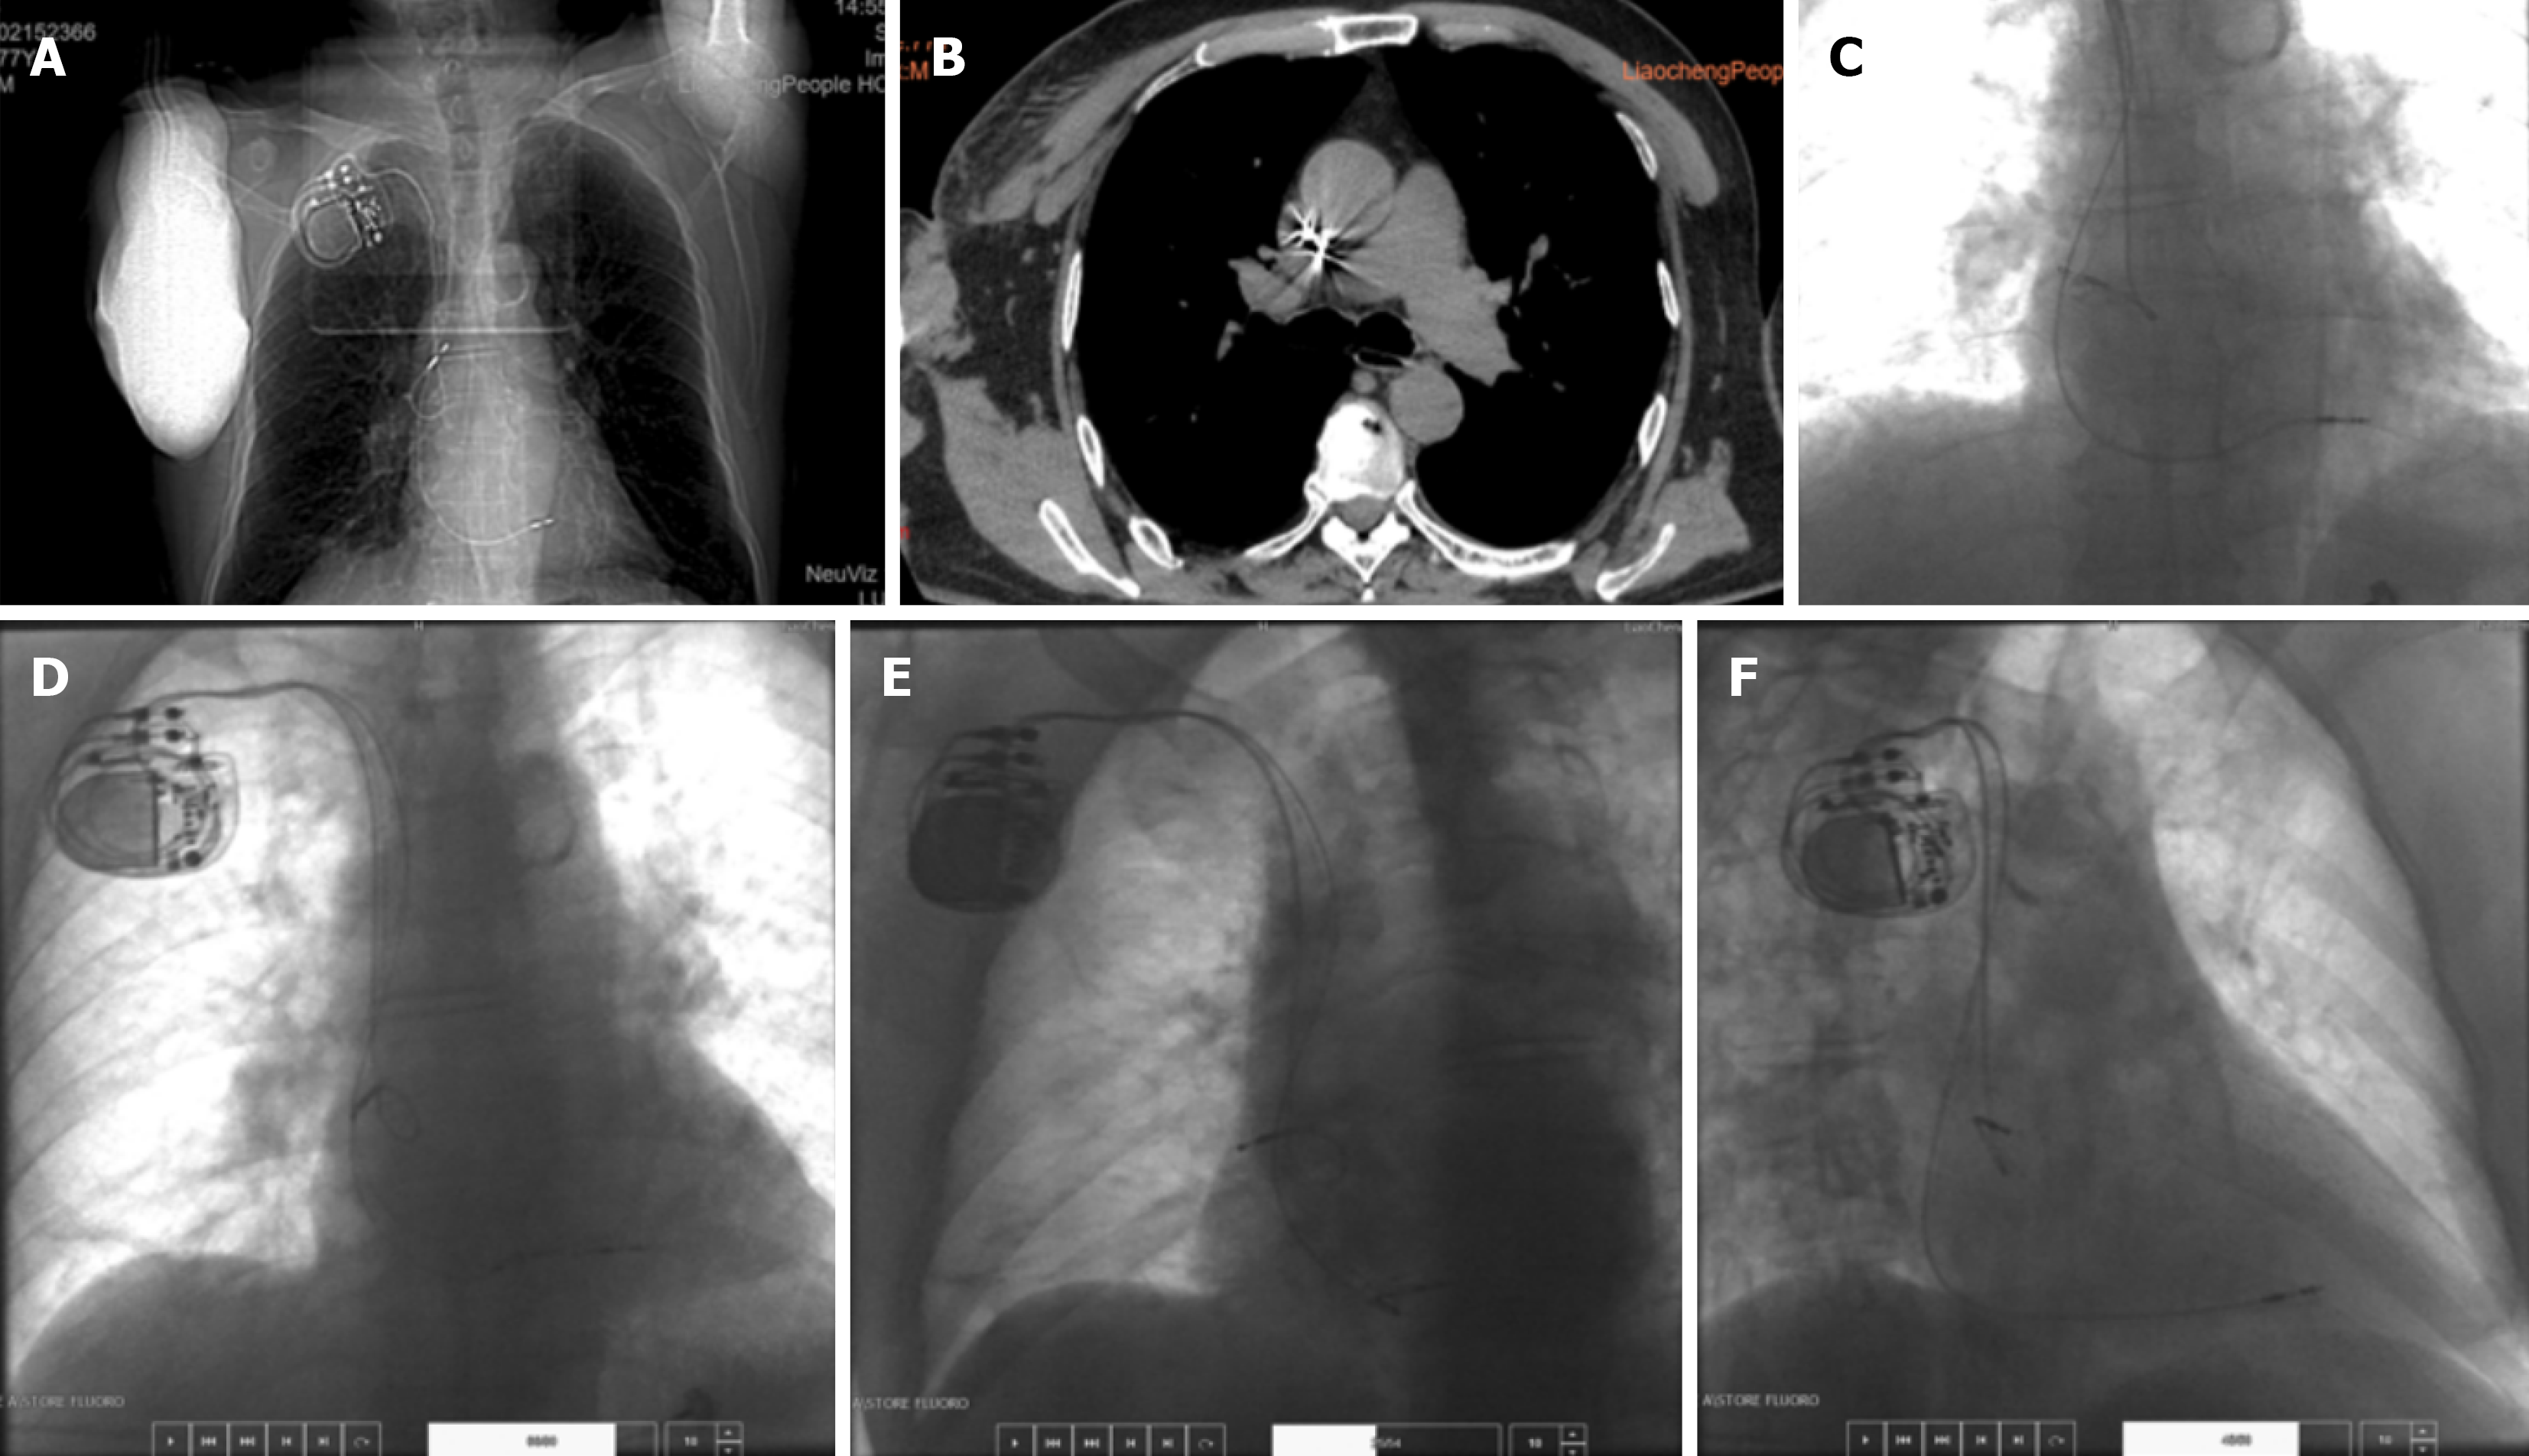

The admission electrocardiogram (ECG) showed third-degree atrioventricular block (III° AVB) (Figure 1), which was considered the cause of his symptoms. A dual-chamber pacemaker implantation was planned under local anesthesia. However, ECG demonstrated poor atrial sensing with normal ventricular sensing and pacing (Figure 1C). Repeat chest radiography and computed tomography (Figure 2A and B) revealed no change in ventricular lead position, but confirmed displacement of the atrial lead compared with its postoperative position. Device interrogation showed loss of atrial sensing. High-output atrial pacing failed to capture the atrium but induced high-frequency diaphragmatic twitching. The frequency of twitching corresponded precisely to the programmed atrial pacing rate. Ventricular impedance, sensing, and threshold remained unchanged, and no diaphragmatic twitching occurred during ventricular threshold testing.

After skin incision and pocket creation, a sheath was introduced. The inner dilator was removed while the guidewire and outer sheath were maintained in place, and a second guidewire was inserted to facilitate lead placement. Resistance was encountered during sheath advancement, but positioning was ultimately successful. An active-fixation ventricular lead (model 2088TC) was implanted in the mid-interventricular septum, and a passive atrial lead (model 1944) was positioned in the right atrial appendage (Figure 2C). Intraoperative parameters were as follows: The atrial sensing voltage was 2.5 mV, the impedance was 680 Ω, and the threshold was 0.6 V; while the ventricular sensing voltage was 6.7 mV, the impedance was 640 Ω, and the threshold was 0.6 V, with a pulse width of 0.4 millisecond for both leads.

An Abbott PM2224 pulse generator was connected and placed in the pocket. The incision was closed. Routine postoperative anteroposterior, left anterior oblique, and right anterior oblique chest radiographs were obtained (Figure 2D-F). Compared with intraoperative images, the atrial lead showed slight rotation after wound closure; however, pacing parameters remained stable, and the procedure was completed. Lidocaine (100 mg) was used for subcutaneous local anesthesia during the procedure, and cephalosporin antibiotics were used for perioperative infection prevention. Immediate postoperative ECG showed atrial sensing with ventricular pacing (Figure 1B).

In this patient, computed tomography imaging after symptom onset demonstrated that the atrial lead tip had migrated to the left posterior aspect of the SVC (Figure 2B). Device interrogation showed absent atrial sensing and diaphragmatic twitching synchronized with atrial pacing stimuli. These findings strongly suggest that electrical stimulation from the displaced atrial lead directly activated the phrenic nerve, resulting in diaphragmatic flutter. Previous studies have also reported phrenic nerve stimulation when active atrial leads were positioned near the interatrial septum.

In this case, the two electrode leads passed through a single puncture point, resulting in the two electrode leads being in close contact and prone to mutual resistance, thus restricting the natural extension of the atrial electrode lead. At the end of the procedure for this patient, the atrial electrode had shifted clockwise to varying degrees (Figure 2D-F). At this time, the resistance between the leads may have prevented the complete release of the clockwise torsional force of the atrial electrode.

In this case, both leads were introduced through a single venous puncture site. The close proximity of the leads likely caused mechanical interaction and resistance, limiting the natural extension of the atrial lead. At the end of the procedure, slight clockwise rotation of the atrial lead was observed (Figure 2D-F). Residual torsional tension may not have been fully released due to friction between the two leads. Postoperative body movements, deep breathing, or coughing may have further released this torsional force, leading to complete atrial lead dislodgement. The displaced lead subsequently stimulated the adjacent phrenic nerve, producing diaphragmatic twitching.